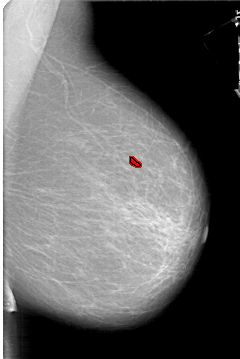

A_1333_1.LEFT_MLO

LEFT_MLO LINES 6541 PIXELS_PER_LINE 4306 BITS_PER_PIXEL 12 RESOLUTION 43.5 NON_OVERLAY

RIGHT_MLO LINES 6451 PIXELS_PER_LINE 4306 BITS_PER_PIXEL 12 RESOLUTION 43.5 OVERLAY

FILE: A_1333_1.RIGHT_MLO.OVERLAY

TOTAL_ABNORMALITIES 1

ABNORMALITY 1

LESION_TYPE CALCIFICATION TYPE PLEOMORPHIC DISTRIBUTION CLUSTERED

ASSESSMENT 4

SUBTLETY 2

PATHOLOGY BENIGN

TOTAL_OUTLINES 1

BOUNDARY